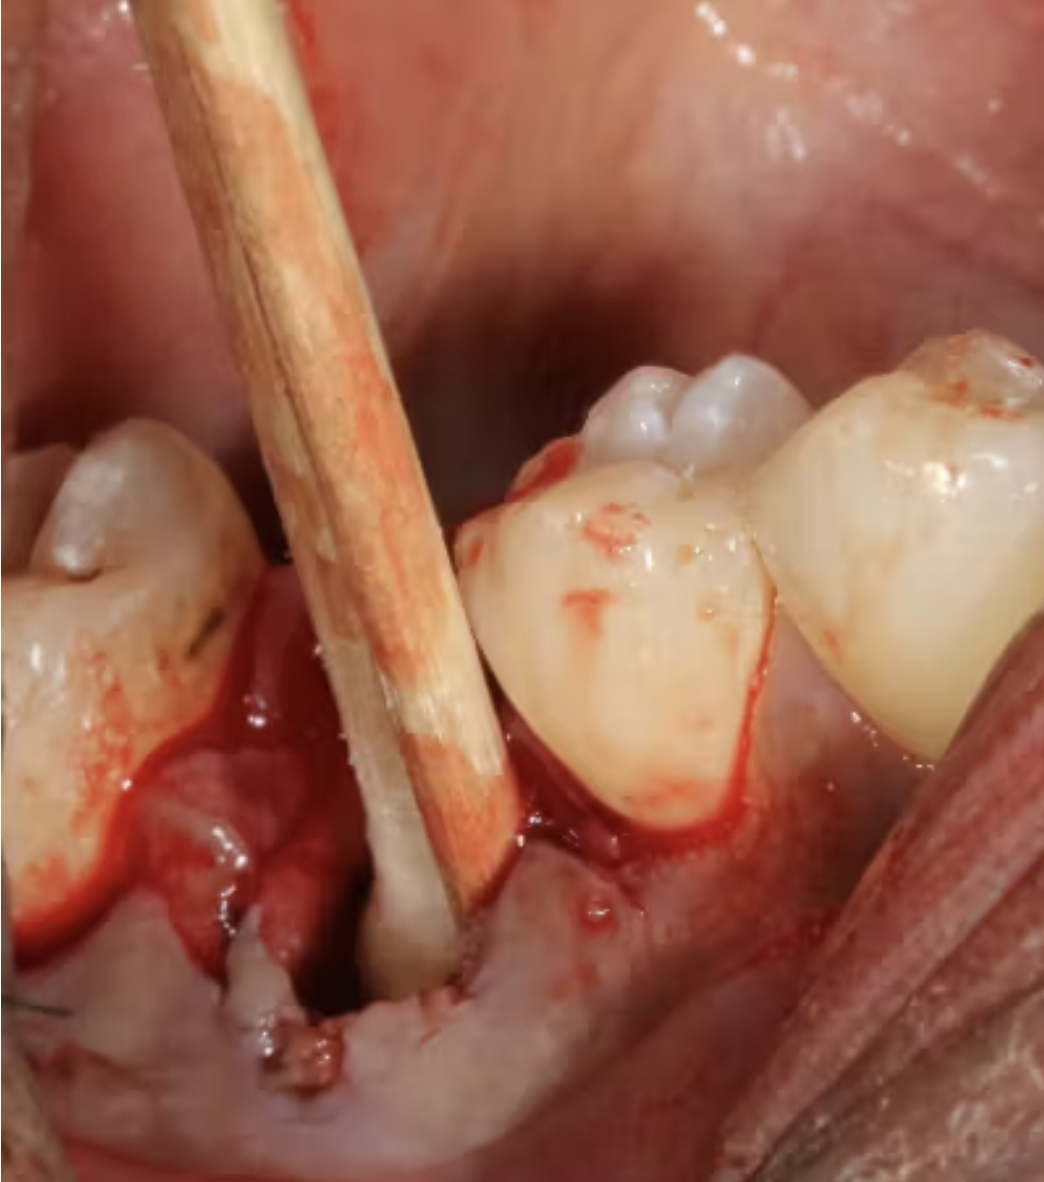

Do đó, cần nạo sạch hoàn toàn ổ implant và loại bỏ kỹ lưỡng tất cả mô mềm trước khi đặt implant mới. Dụng cụ phải đủ sắc để có thể tiếp cận đến đáy ổ implant và cạo sạch thành xương quanh ổ.

(Hình 2: Dụng cụ Slade Blade socket curette được sử dụng để lấy bỏ mô sợi trong ổ implant còn lại)